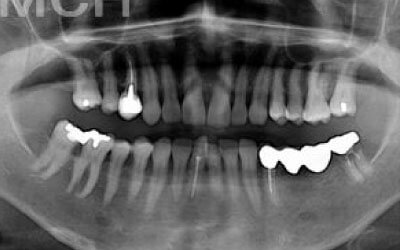

ブリッジとインプラントでは、前後の歯の寿命に大きな違いがあります。ブリッジでは、支えとなる歯を虫歯がなくても大きく削る必要があり、さらに噛む力が通常の1.5倍かかるため、その寿命が短くなりがちです。実際の統計によると、ブリッジの支えとなる歯の68%が、10年以内に抜歯を余儀なくされるという結果が出ています。

噛むとき、誰でも歯に何十キロもの力がかかっています。当然、歯の本数が減れば減るほど、残った歯にかかる負担は大きくなります。ブリッジ治療の場合、失われた歯にかかっていた力は、前後の歯で支えることになります。その結果、残った歯には、抜歯していないときに比べて1.5〜2倍程度の力がかかることになります。

ブリッジなどの治療では、前後の歯を大きく削る必要があります。場合によっては、虫歯がないのに歯の神経を取らなければならないこともあります。実際、神経を取って被せ物をすると、その歯は一気に「最終段階」に進んでしまうのです。しかし、インプラント治療では、前後の歯を削ることも、神経を取ることもありません。歯の寿命を延ばすためにも、健康な歯をできるだけ削らないことが非常に重要なのです。

歯科の統計データをご紹介します。

インプラントは、10年経っても約90~95%の確率で問題なく使い続けられています。

一方、ブリッジの場合は、10年後に残っているのは約30~35%にとどまります。

ブリッジが使えなくなる主な原因は、支えている歯が悪くなり抜歯が必要になるケースがほとんどです。

最も大きな違いは、前後の歯の寿命に影響が出ることです。

ブリッジの場合、抜けた部分の前後の歯を大きな虫歯と同じくらい削る必要があります。

また、抜けた歯の力を前後の歯が支えているため、ブリッジを支える歯には常に1.5倍の負担がかかることになります。

ブリッジの支えの歯は、データでは10年以内に68%が抜歯になります。